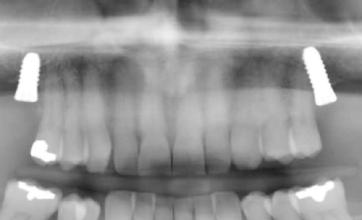

20–22. ábra: 2017-es, 2019-es és 2022-es panorámaröntgen-felvételek.

Információ, hirdetésfelvétel: Kiss Éden Aliz, telefon: 06-30-472-0030

Az újság e-mail címe: info@dental.hu

Az újság internetcíme: www.dental.hu